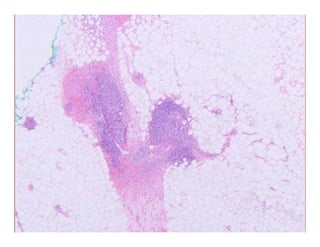

Cas130Cas130Cas130Cas130

ParaffinomaParaffinoma

k S l i li lk S l i li laka…Sclerosing lipogranulomaaka…Sclerosing lipogranuloma

Special form of facticial panniculitis resulting from injection of lipiSpecial form of facticial panniculitis resulting from injection of lipi

(often paraffin) into subcutaneous tissue(often paraffin) into subcutaneous tissue

Well circumscribed noduleWell circumscribed nodulee c cu sc bed odu ee c cu sc bed odu e

? Swiss cheese appearance? Swiss cheese appearance

Bands of hyaline fibrous tissue between fat cells and cystic spacesBands of hyaline fibrous tissue between fat cells and cystic spaces